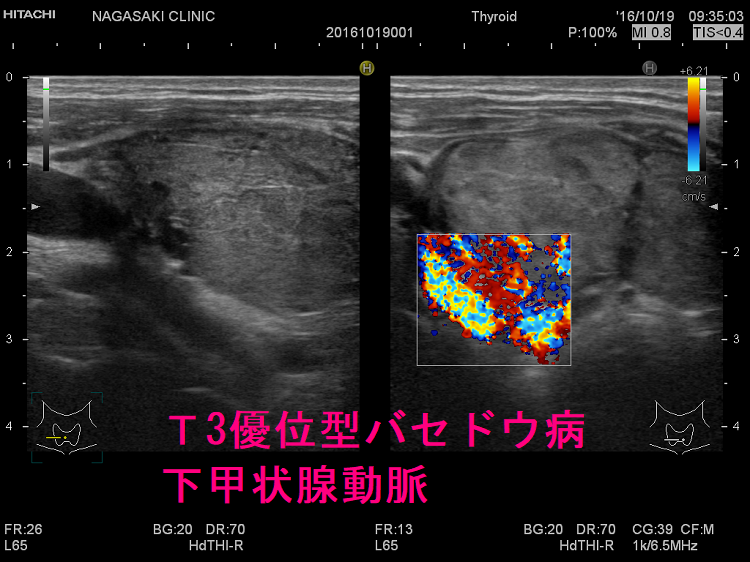

ケース② 巨大甲状腺腫・甲状腺内部血流増大

難治性T3優位型バセドウ病は若年女性に多く、甲状腺組織の2型脱ヨード酵素(DIO 2)活性が異常に高いため、FT4に比べFT3が著明高値になる。巨大甲状腺腫、TSH レセプター抗体(TRAb)異常高値、甲状腺超音波エコー検査で下甲状腺動脈は異常に太く、下甲状腺動脈血流速度ITA-PSVも異常高値。薬物治療抵抗性で、FT4正常化してもFT3は高値、再発繰り返す。I-131治療は1回で終わらず、甲状腺全摘出手術になる。服薬アドヒアランス不良は患者がメルカゾール・プロパジールを服用しない事。難治性バセドウ病と思って薬を増やしても、甲状腺ホルモンは下がらない。

T3優位型バセドウ病は、甲状腺機能亢進症/バセドウ病の約10%を占めるとされ、若年女性に多く、巨大甲状腺腫、TSH レセプター抗体(TRAb)異常高値が特徴。